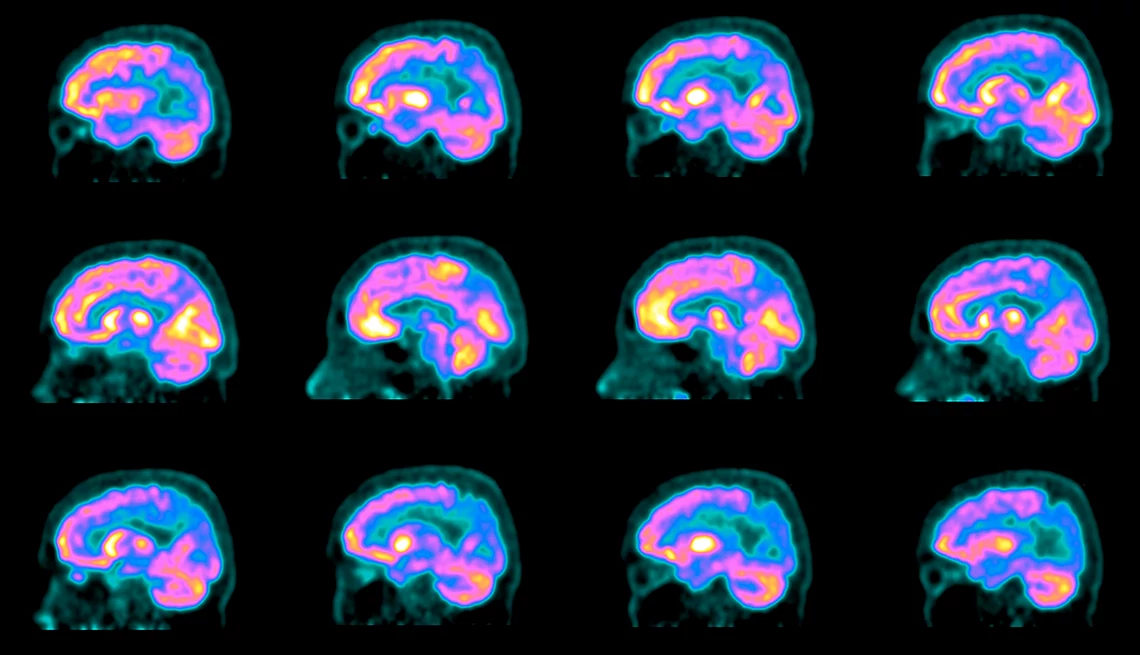

That was in 2018. One year later, Chayrez, 58, was diagnosed with mild cognitive impairment, and shortly thereafter, Alzheimer’s disease. Since June 2023, he has received twice-monthly infusions of lecanemab (Leqembi), the headline-grabbing medication approved last year by the Food and Drug Administration that removes Alzheimer’s hallmark plaques from the brain and slows down memory loss. “I think I’ll have more days of happiness,” Chayrez says.

It comes with dangers of its own, including the risk of brain swelling and bleeding. Studies are ongoing. But despite all these drawbacks, it represents a huge breakthrough, a foundation on which the medical community can finally begin to build.

Yet after more than 40 years of studies, tens of billions in research funding, at least 146 failed drugs and plenty of public controversy and private despair among scientists, the approval of lecanemab marks a major turning point in the fight against Alzheimer’s. It’s the first “disease-modifying” drug for Alzheimer’s to receive traditional FDA approval and win standard Medicare coverage. Most significantly, lecanemab is one in a handful of recent advances expected to — at last — transform how the medical community diagnoses, treats and eventually prevents one of America’s most-feared diseases.

Once it begins, there’s no way to halt it. As brain cells die, connections between them wither and the brain itself shrinks, memory worsens, thinking skills decline and navigating everyday life becomes less and less possible. At least a third of people with early-stage Alzheimer’s slip into a more severe stage in about three years, putting lecanemab and possibly other early-stage treatments out of reach. Because heredity plays a role, many of us with a family history of Alzheimer’s have long looked to the future with dread.